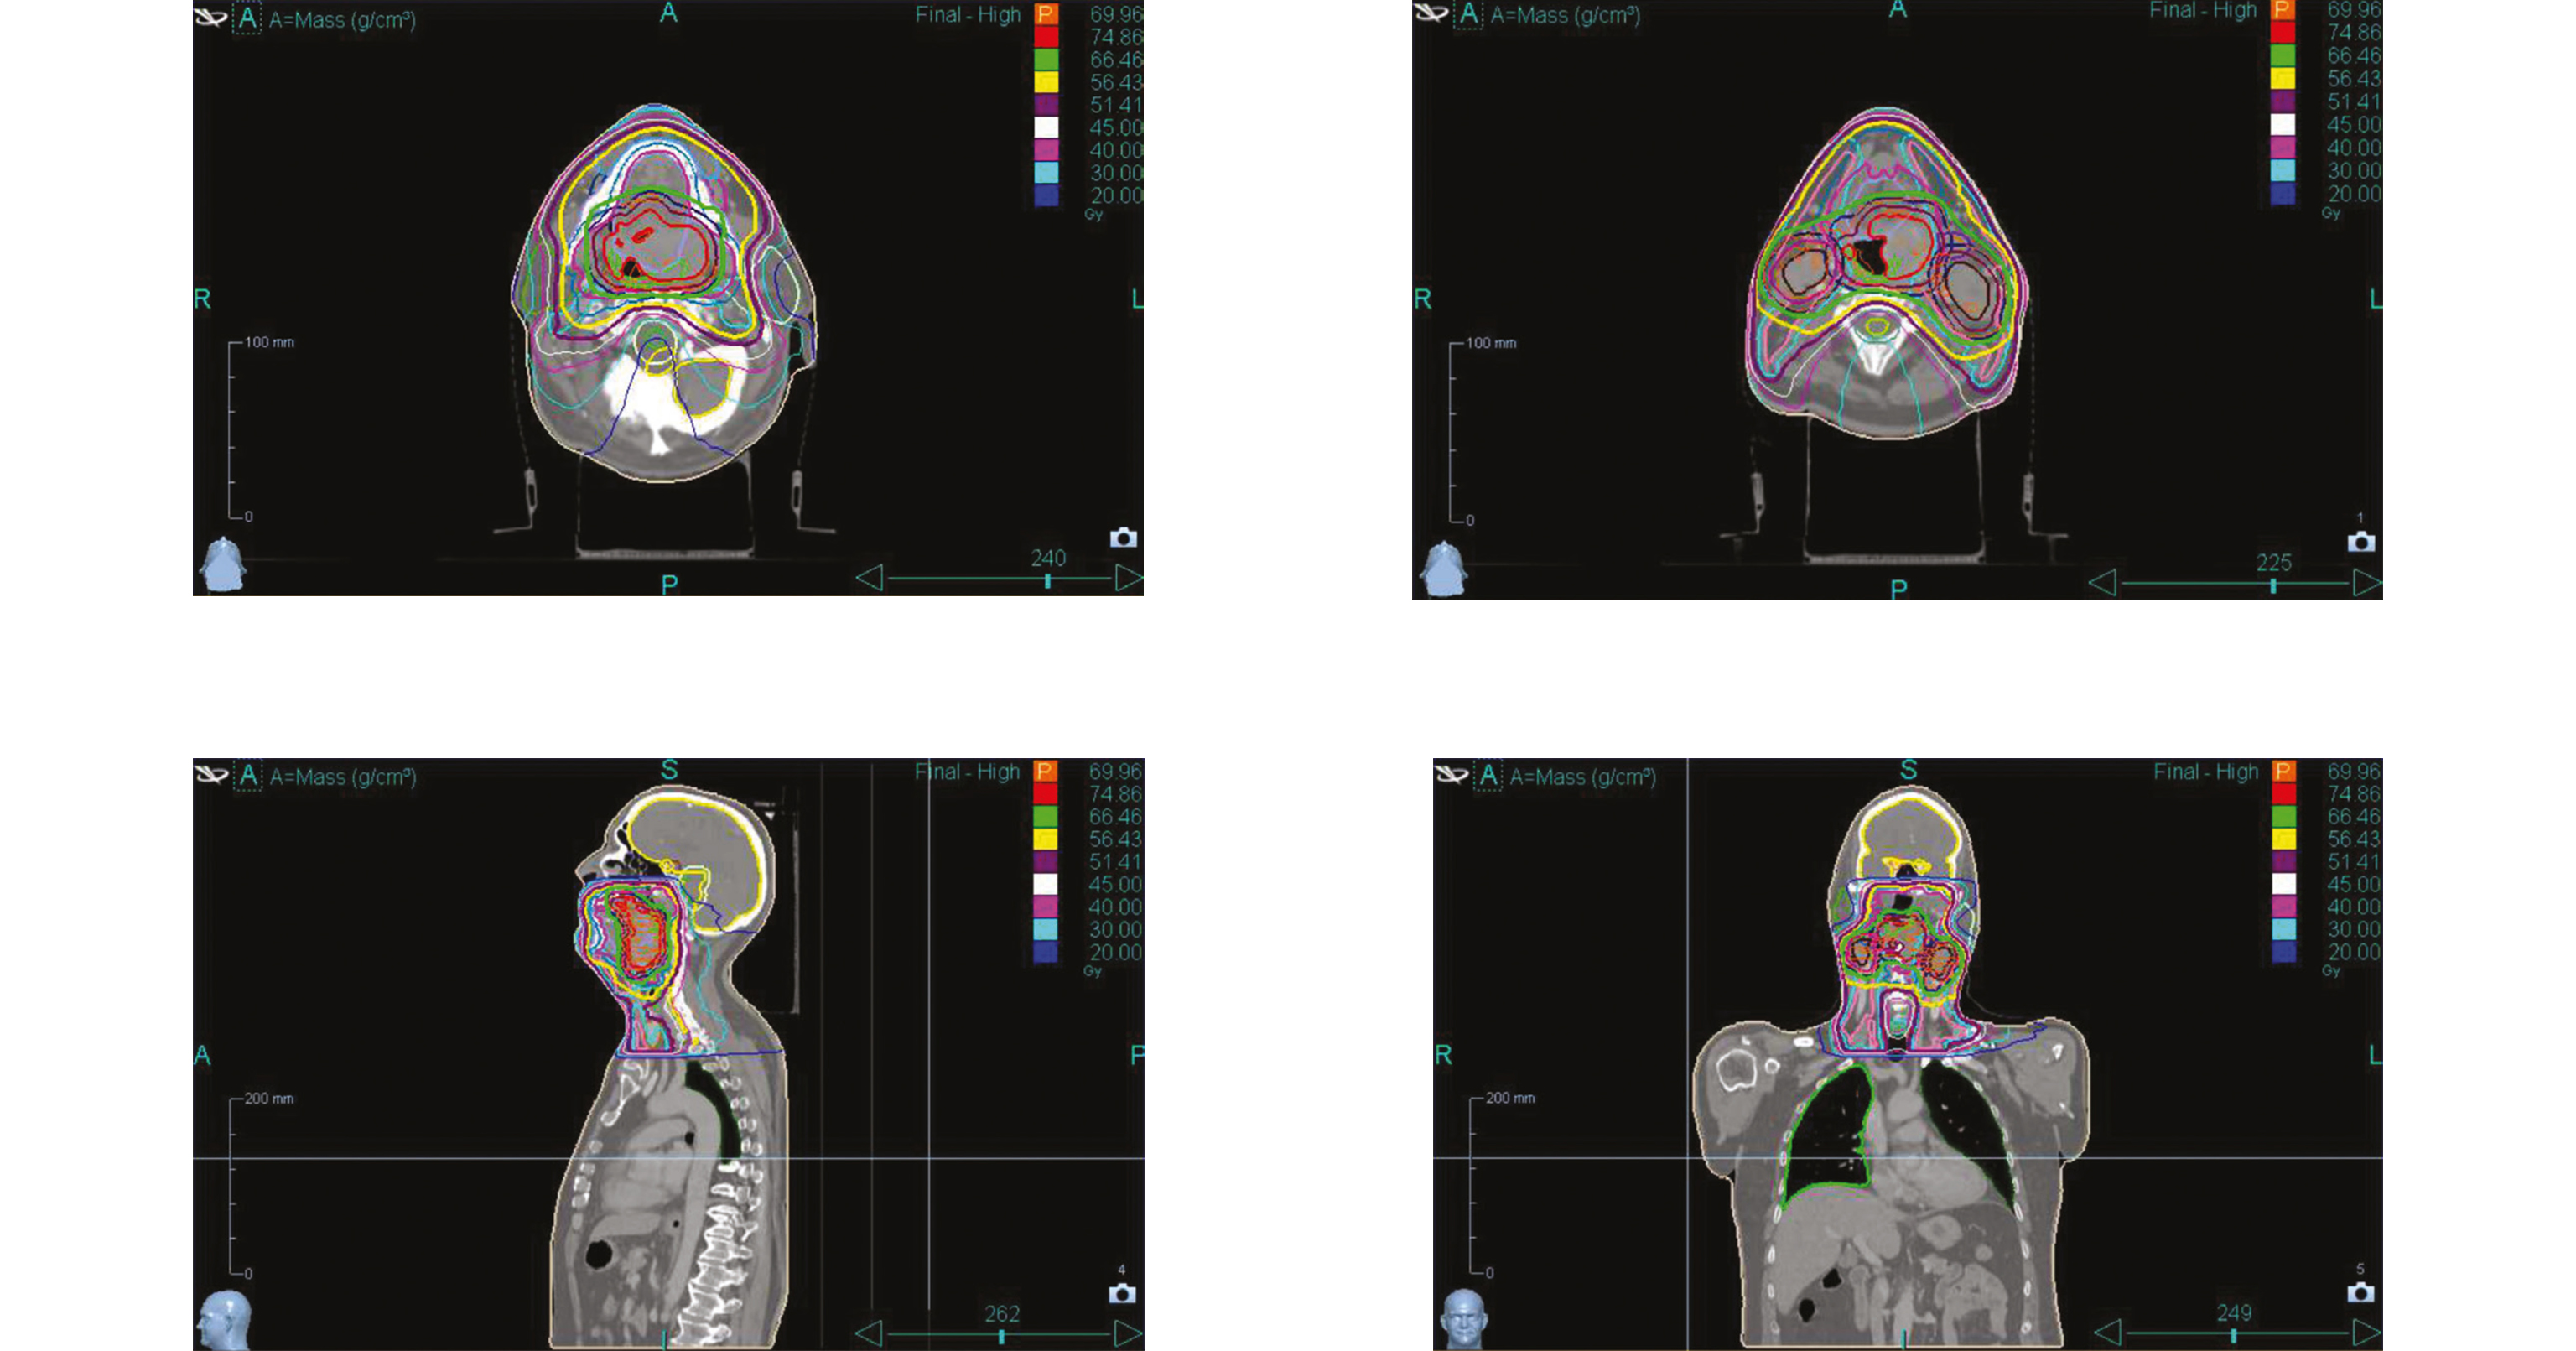

Lors de la consultation initiale avec l'oncologue radiothérapeute, un suivi infirmier en pratique avancée (IPA) pendant la radiothérapie ainsi qu'un traitement par photobiomodulation en prévention des toxicités radio-induites sont proposés et acceptés par le patient. Ce dernier refuse cependant la pose préventive d'une gastrostomie endoscopique percutanée (GEP). Un bilan dentaire, un bilan audiométrique ainsi qu'une consultation diététique sont réalisés avant le début du traitement.

Dans le cas de ce patient, la survenue rapide d'effets secondaires majeurs a nécessité une prise en charge intensive et coordonnée entre médecins et IPA, permettant d'anticiper les complications, de limiter les interruptions de traitement, d'éviter replanification du scanner de centrage, et de maintenir une qualité de soins optimale grâce à la coordination intra- et extrahospitalière.